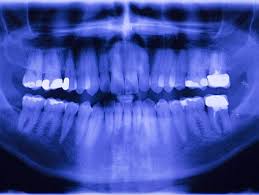

X Rays Uses Procedure Results

X Rays Uses Procedure Results from www.verywellhealth.com

In the case of standard procedures, there is no or negligible chance of risk. The lowest radiation exposure to cause radiation sickness is about 100 rem (1 sv). This level of exposure will also increase your risk of a fatal cancer over the next few to several decades by about 5%. More images for how many x rays are safe in a year » Why are x rays dangerous? How many x rays are dangerous? They are advised only at certain ages. What matters is the intensity of the radiation.